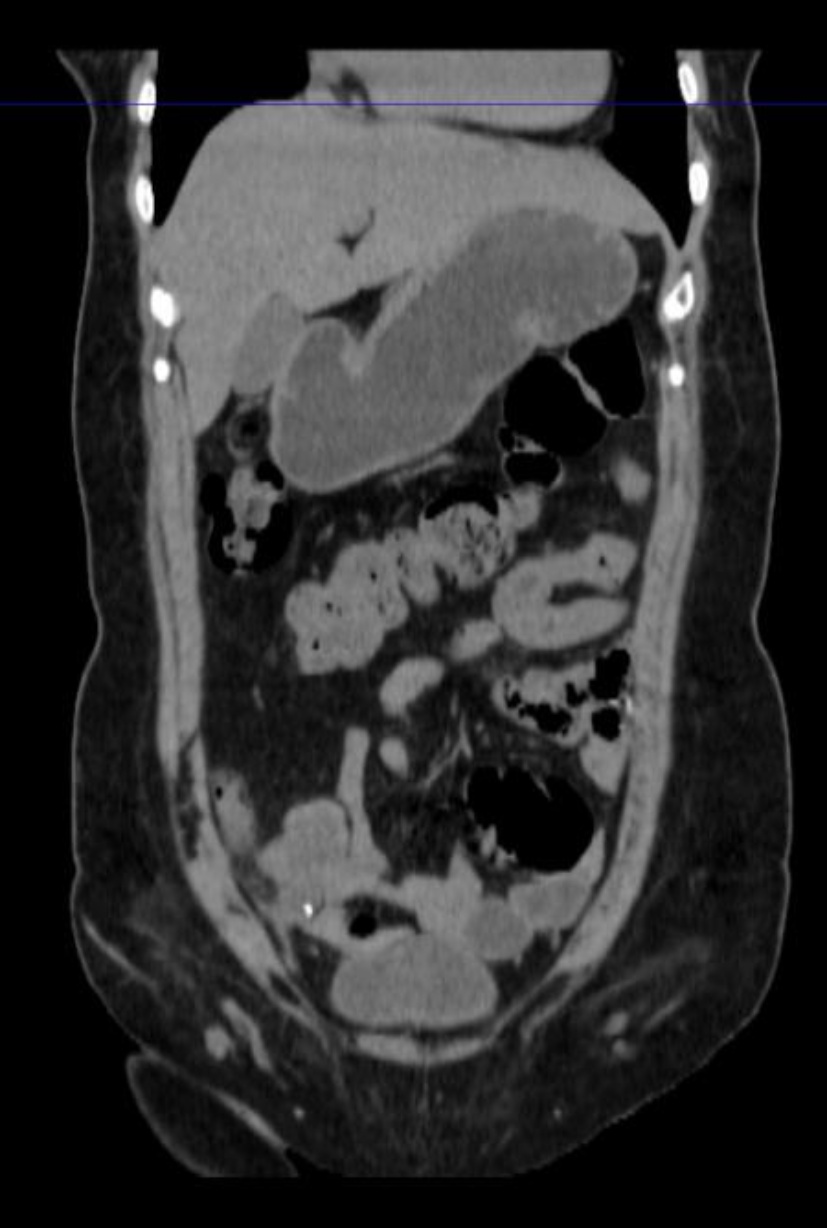

出院后患者为行扩大根治手术,来我院就诊。给进一步完善相关检查,腹部增强CT示:

患者阑尾未见明确显示,相应区短条状高密度影,周围条片及淋巴结影,边欠清,部分轻度强化征象,局部肠壁模糊,右下腹肠系膜及大网膜条片影,边欠清。区段小肠肠壁明显增厚,考虑肿瘤可能性大(见图4(a)图4(b))。经多学科讨论后,考虑患者阑尾肿瘤合并小肠肿瘤可能性大,各项术前检查未见明显转移征象,建议再次行手术探查。术中见:肝周及盆底血性积液,量约100 ml,部分小肠黏连与腹壁原切口下方,顿性分离黏连肠管,部分小肠、大网膜黏连固定于右下腹回盲部,松解黏连后,见回盲部、临近小肠系膜、大网膜及右侧腹壁触及质硬结节,距回盲部2 m处小肠肠管明显增粗、质硬,肝脏表面光滑,无明显占位。给予切除距回盲部远端10 cm升结肠及近端10 cm回肠,行回肠及升结肠吻合。切除距回盲部2 m处病变小肠,行小肠吻合。术后病理示:(距回盲部2 m处小肠):黏液癌(隆起型,3 × 2 cm),肿瘤侵透浆膜,脉管癌栓(−),神经侵犯(+),两侧手术切缘未见癌累及,肠周淋巴结内未见癌转移(0/2) (见图5图6)。(回盲部小肠):送检小肠组织,黏膜慢性炎,浆膜面及肠系膜内出血、纤维组织及间皮增生并见少许无上皮黏液,两侧切缘未见癌累及,肠周淋巴结内未见癌转移(0/10)。病理分期:pT4bN0Mx。(右半结肠)送检肠管组织,浆膜面见少量异型腺体浸润,意见为癌。周围组织呈异物肉芽肿性炎,两侧手术切缘未见癌累及,肠周淋巴结内未见癌转移(0/21)。(腹膜结节)送检组织内纤维组织结节状增生。(大网膜)网膜组织内见多处纤维组织增生伴异物巨细胞反应。经多学科会诊讨论后,考虑患者诊断原发肿瘤来自小肠,阑尾肿瘤为小肠侵犯所致。术后患者于肿瘤科行3周期Xelox方案化疗:奥沙利铂130 mg/m2,静脉输注2 h,第1天。卡培他滨每次1000 mg/m2,每日2次,第1~14天。患者术后随访至今未见异常。

(a) (b)

Figure 4. Abdominal CT (Before the second surgery)

4. 腹部CT(第二次手术前)